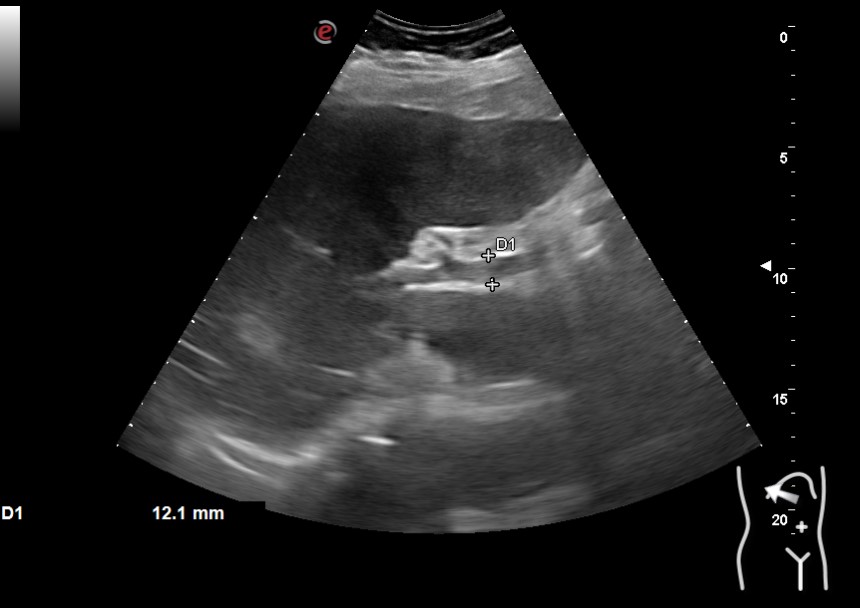

Hallazgos ecográficos

Vesícula biliar desestructurada, de paredes mal definidas con litiasis de 20 mm, que contacta con la pared de la segunda porción duodenal. Porta de tamaño normal. Vía biliar no dilatada.